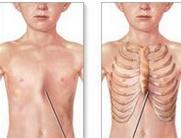

• 胸壁軟組織畸形

胸壁軟組織畸形是指乳房、胸大肌、胸小肌發(fā)育不全和缺如。可分為先天性和后天性兩類。先天性主要指Poland綜合征,而后天的胸壁畸形多見于各種類型的胸部外傷和某些疾病如腫...